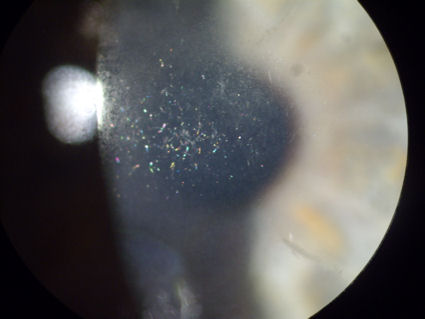

На этом глазу, представленном на фотографии ниже, были проведены 2 отдельные операции по удалению RK, за которыми последовали 2 отдельные процедуры LASIK. Последняя операция по удалению LASIK у этой пациентки была проведена в 2004 году. В 2013 году под лоскутом LASIK левого глаза была обнаружена большая колония эпителиальных клеток. Через год эта группа эпителиальных клеток распалась и мигрировала в центральную область роговицы под лоскутом LASIK. "Блестящее" изображение, показанное на этой фотографии, на самом деле представляет собой эпителиальные клетки, которые мигрировали с поверхности роговицы в области под лоскутом LASIK. Недавно специалист по роговице из всемирно известного офтальмологического института отказался приподнять лоскут LASIK, чтобы удалить остатки клеток, которые сейчас находятся под ним. (Яркий белый свет, видимый в левой части фотографии, является отражением лампы в микроскопе.) Нажмите на изображение, чтобы увеличить.